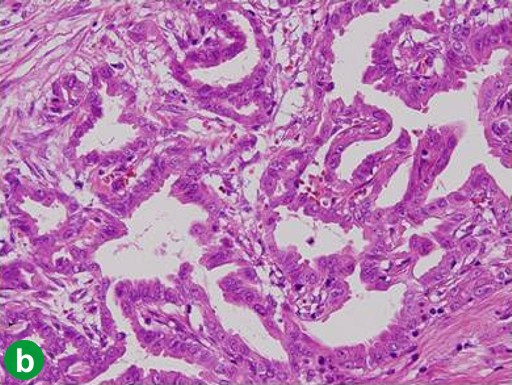

A 65-year-old man showed a dilatation of the main pancreatic duct on abdominal US at an annual medical checkup. An abdominal CT scan showed a 1 cm tumor in the head of the pancreas (Figure 1a), and dilatation of the main pancreatic duct in the distal part of the pancreas was demonstrated by MRCP (Figure 1b). A pylorus-preserving pancreaticoduodenectomy (PPPD) was performed in December 2000. The tumor was confirmed histopathologically to be a well-differentiated adenocarcinoma without lymph node metastasis (T1N0M0; R0; pathological stage: IA) (Figure 1c). Although the surgical margins were negative, pancreatic intraepithelial neoplasia was present in the resected pancreas. Adjuvant chemotherapy (4 cycles of 5-fluorouracil, leucovorin and mitomycin C given intravenously) was administered for 4 months. Periodic check-ups were performed thereafter.

|

Figure 1. Case#1: initial operation. a. A tumor approximately 1 cm in diameter was detected in the pancreatic head on abdominal CT (arrow). b. The main pancreatic duct was disrupted, and the main pancreatic duct of the distal pancreas was dilated on MRCP. c. Well-differentiated tubular carcinoma. Marked fibrosis and acinus atrophy were observed. Mild atypical cells with a slightly swollen nucleus formed an irregular ductal structure and invaded the parenchyma. (H&E stain, x100). |